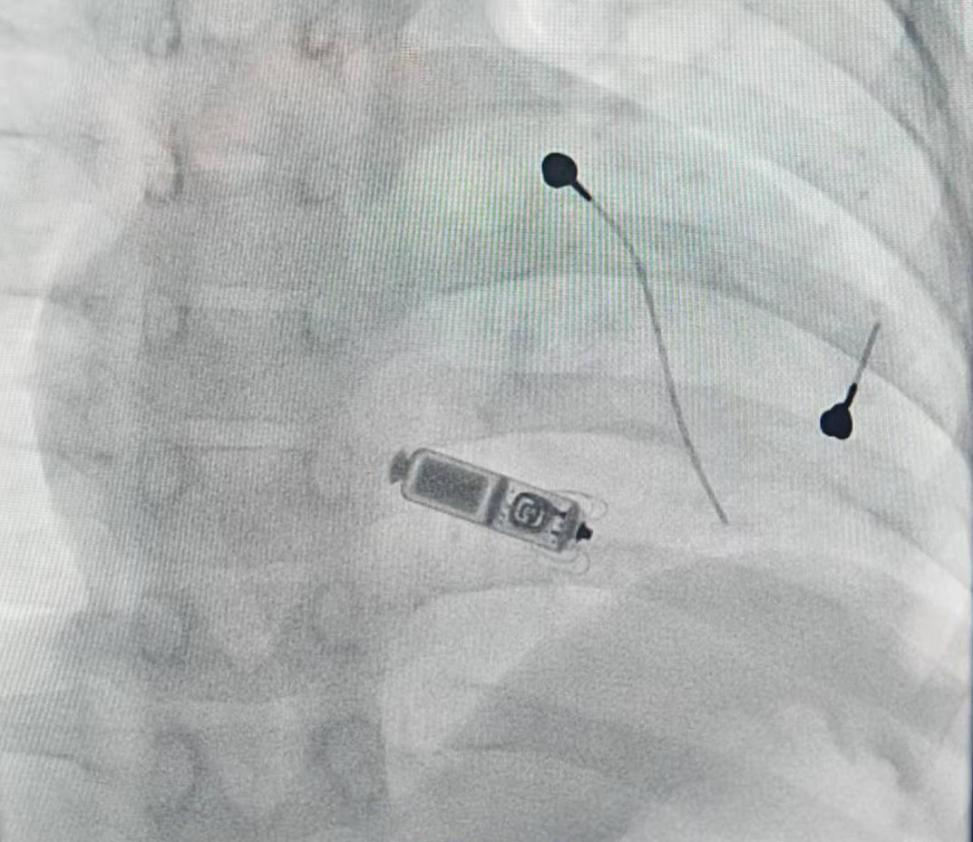

心血管内科副主任江河主刀,凭借精湛技艺和丰富经验,在极小的操作空间内小心翼翼推进,通过颈内静脉精准送入输送鞘管,将无导线起搏器稳稳放置于小文心脏的最佳起搏位置。术中测试显示,起搏器参数完全达标、固定牢靠;心脏超声检查未发现心脏穿孔、三尖瓣反流等问题;最后以“8字缝合”处理创口,无出血、无闭塞。

当无导线起搏器成功启动,小文的心脏重新恢复规律有力地跳动,伴随小文的生命危机随之化解。守在手术室外的家长闻讯,喜极而泣。